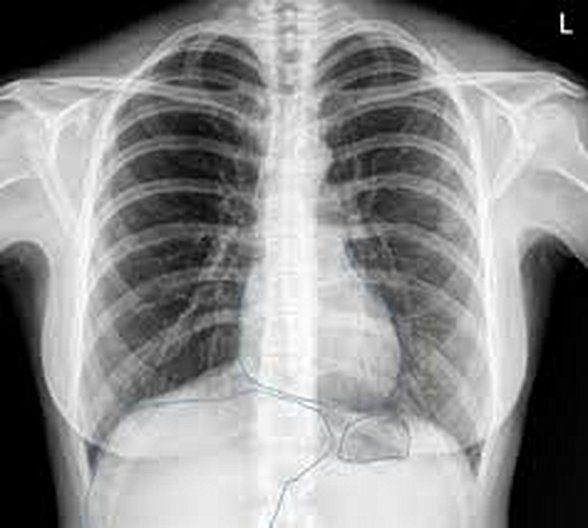

Bir röntgen filminde kemiklerin daha beyaz, akciğer gibi organların siyah olarak görünmesinin temel nedeni kemiklerimizde bulunan kalsiyum (Ca) atomunun atom numarasının 20, akciğerimizde bulunan havanın temel bileşiminde yer alan oksijenin (O) 8 ve azotun (N) 7 atom numarasına sahip olmasıdır. X ışınları akciğerden geçerden daha az absorbe olurken kemik gibi dokularda çok daha fazla absorbe olarak röntgen filminde kontrast yaratmaktadır. Böylece farklı doku ve organlar birbirinden ayırt edilebilmektedir.